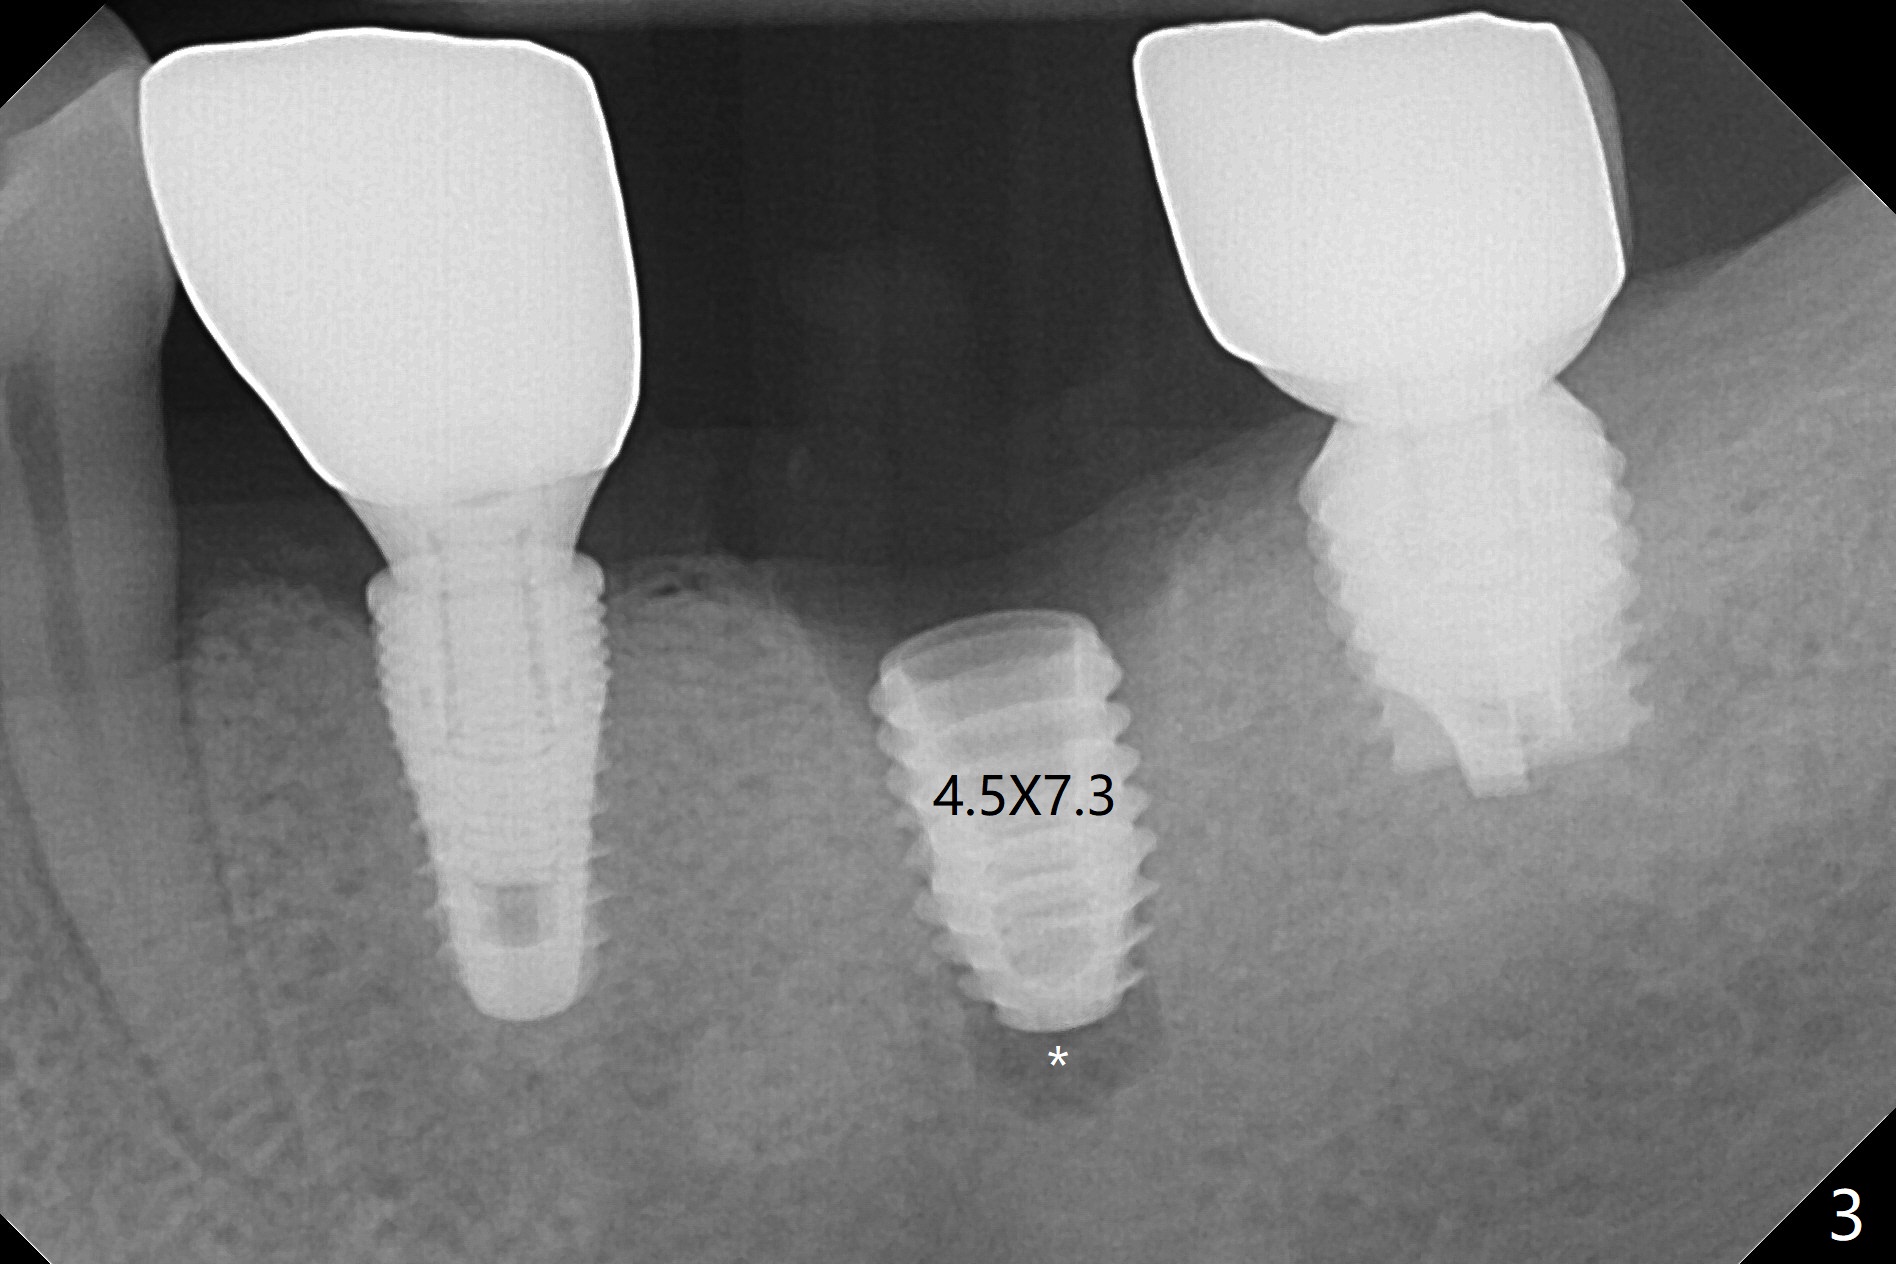

Since there is ~ 2 mm bone apical to the 5x8 mm loose implant at #19 (Fig.1), primary stability is achieved for a 4.5x10 mm dummy IS implant (having better surface treatment than the previous implant) when osteotomy is finished with a 4 mm drill (Fig.2). It is the same associated with a 4.5x7.3 mm definitive one with apical space (Fig.3 *). After depth adjustment to make sure that the implant is subcrestal circumferentially, sticky bone is placed on the top of the implant and around the implant at #18 (Fig.4 *), followed by PRF membranes and suturing with 5-0 PGA and 4-0 Chromic gut suture. Periodontal dressing is applied around the cemented abutment at #18 for additional retention. There is no paresthesia postop. In fact immediate implant redo is fairly safe. The wound heals 1 month postop (Fig.5). There is reorganized bone coronal to the healing screw 4 months postop (Fig.6), which is confirmed in uncovering. One month post uncover, the 6x4 mm healing abutment is found to be loose, suggesting incomplete seating after uncover. A 5.2x4.5(4) mm cemented abutment seems to be incompletely seated (Fig.7). It remains the same after 5.5 and 6.0 mm profile drills (Fig.8,9). A 4.5x4.5(4) mm abutment appears to be completely seated (Fig.10). When the crowns of #18 and 19 are cemented, the gingival embrasure between them is narrow (Fig.11 ^) because of bulky porcelain build-up (*). The tooth #21 with buccal Class V defect (Fig.12 *) seems to have occlusal trauma 1 year 6 months post cementation of #18 and 19. The problems are subsequently taken care of.